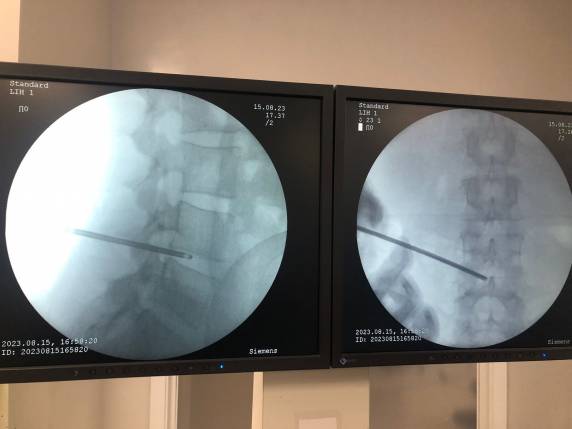

A realização de procedimentos minimamente invasivos é uma tendência que cresce cada vez mais. E até mesmo patologias mais comuns podem ser tratadas através de cirurgias realizadas por vídeo, como é o caso da hérnia de disco. Recentemente, foi realizado no Centro Cirúrgico do Hospital Vida & Saúde, uma cirurgia percutânea de hérnia – a primeira deste tipo realizada no município.

Realizada a partir de uma pequena incisão, sem necessidade de abertura cirúrgica da coluna. Especialista em cirurgia de coluna, o médico Vanderlei Sartor explica que a cirurgia percutânea de hérnia é indicada de acordo com a gravidade de cada caso. Diferentemente da cirurgia convencional, este tipo de procedimento possibilita uma recuperação mais rápida. “É um procedimento de alta resolutividade, com pouco sangramento e que possibilita uma alta precoce e a volta mais rápida às atividades de rotina do paciente”, destaca.

Em procedimentos convencionais, o paciente passa por um processo mais invasivo, que ocasiona em uma internação hospitalar mais prolongada. No caso da cirurgia realizada no HVS, o paciente recebeu alta oito horas após a cirurgia.